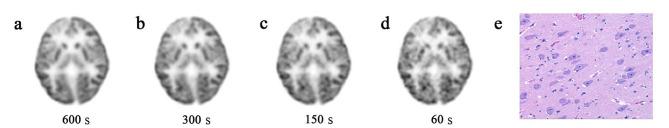

F-FDG positron emission tomography (PET) plays a crucial part in the evaluation for pediatric epileptic patients prior to therapy. Short-term scanning holds significant importance, especially for pediatrics epileptic individuals who exhibited involuntary movements. The aim was to evaluate the effects of short acquisition time on image quality and lesion detectability in pediatric epileptic patients using total-body (TB) PET/CT. A total of 25 pediatric patients who underwent TB PET/CT using uEXPLORER scanner with an F-FDG administered dose of 3.7 MBq/kg and an acquisition time of 600 s were retrospectively enrolled. Short acquisition times (60 s, 150 and 300 s) were simulated by truncating PET data in list mode to reduce count density. Subjective image quality was scored on a 5-point scale. Regions of interest analysis of suspected epileptogenic zones (EZs), corresponding locations contralateral to EZs, and healthy cerebellar cortex were used to compare the semi-quantitative uptake indices of short-time images and then were compared with 600 s images. The comparison of EZs detectability based on time-dependent PET images was performed.

RESULTS

Our study demonstrated that a short acquisition time of 150 s is sufficient to maintain subjective image quality and lesion significance. Statistical analysis revealed no significant difference in subjective PET image quality between imaging at 300 s and 150 s (P > 0.05). The overall impression scores of image quality and lesion conspicuity in G60s were both greater than 3 (overall quality, 3.21 ± 0.46; lesion conspicuity, 4.08 ± 0.74). As acquisition time decreased, the changes of SUVmax and SD in the cerebellar cortex gradually increased (P < 0.01). There was no significant difference in asymmetry index (AI) difference between the groups and the AIs of EZs were > 15% in all groups. In 26 EZs of 25 patients, the lesion detection rate was still 100% when the time was reduced to 60 s.

CONCLUSIONS

This study proposed that TB PET/CT acquisition time could be reduced to 60 s with acceptable lesion detectability. Furthermore, it was suggested that a 150 s acquisition time would be sufficient to achieve diagnostic performance and image quality for children with epilepsy.